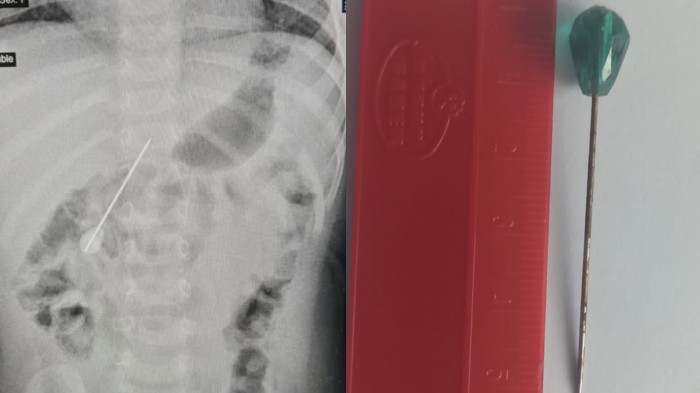

PILU Bayi 7 Bulan Kritis Setelah Menelan Jarum 5,5 Cm hingga Menancap di Usus saat Ibadah Umrah

Akibat menelan jarum 5,5 cm, bayi umur 7 bulan sampai dilarikan ke rumah sakit karena kritis.

Baru-baru ini, seorang bayi berusia tujuh bulan asal Amerika Serikat membuat gempar karena dilarikan ke rumah sakit di Makkah setelah menelan jarum 5,5 cm.

Dalam kondisi kritis, bayi perempuan itu dilarikan ke unit gawat darurat Rumah Sakit Bersalin dan Anak-anak Makkah karena jarum menancap di ususnya hingga menyebabkan lubang luka, dikutip dari OHBULAN!, Jumat (24/6/2022).

Meski sulit karena faktor usia bayi dan juga ukuran jarum, tetapi tim medis yang bertugas akhirnya mampu mengeluarkan jarum tanpa operasi.

Menurut kepala tim medis, Dr. Abdullah Al-Shanbary, setelah prosedur berhasil, bayi tersebut dipuasakan selama empat hari untuk menjalani pemeriksaan dan pemindaian sinar-X.

Kabar baiknya, hasil rontgen menunjukkan bahwa luka dalam bayi telah sembuh.